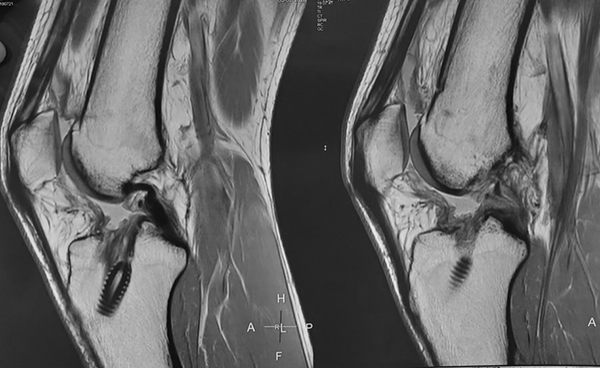

Al examen físico se evidenciaba rodilla derecha con recurvatum (paciente hiperlaxo), tumefacta, con moderado derrame articular y presencia de choque patelofemoral, limitación del rango de movilidad por dolor, maniobras de Lachman (+++/+++) y Pivot shift (+++/+++, explosivo), signos meniscales internos y externos, translación y rotación interna tibial. Se solicitó un par radiográfico de esa rodilla, en la que se evidenciaron túneles femorales y tibiales realizados con técnica anatómica (transportal medial) con satisfactoria ubicación y orientación, sin aumento de tamaño significativo (diámetro y longitud) (fig. 1). Se evaluó específicamente la pendiente o slope tibial, sin encontrarla aumentada. Debido a esto no se consideró necesario complementar estudios de imágenes preoperatorios con tomografía computada (TAC).

Figura 1: Rx rodilla derecha frente y perfil.

Se realizó control radiográfico postoperatorio, y se constató correcta posición de túneles y material de fijación. Rótula en buen estado (fig. 8).

Figura 8: Rx postoperatoria de rodilla derecha. Rótula, túneles e implantes de fijación en buen estado.